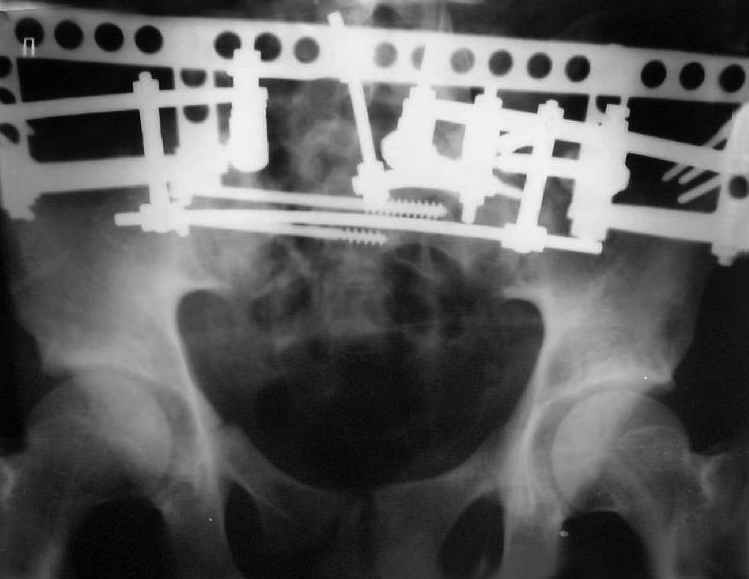

Уважаемые коллеги! Хотел-бы обсудить варианты лечения больной с застарелым переломом таза. Возраст 40 лет. Травма 11 месяцев назад. Главный травматолог Камчатского Военно-морского госпиталя Юрий Алексеевич Булахтин

У больного судя по всему вертикальная деформация таза. А каковы основные жалобы пациента и какие у него функциональные требования?

Мы, как правило, в подобных случаях проводим оперативное лечение в несколько этапов. Первым устраняем деформацию при помощи АВФ (кольцевой конструкции с фиксацией задних отделов), вторым- выполняем введение илиосакралых винтов, накостный остеосинтез передних отделов.

Для информации к размышлению о возможности исправления имеющейся деформации предлагаю похожий случай.